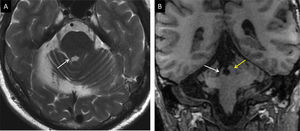

Niño de 3 años con infarto antiguo de arteria cerebral media derecha. Imágenes evolutivas potenciadas en T2 muestran la pérdida de volumen talámico (punta de flecha en A) por degeneración transináptica retrógrada de las proyecciones tálamo-corticales y del pedúnculo cerebral derecho (flecha amarilla en B) por degeneración walleriana del haz corticoespinal.